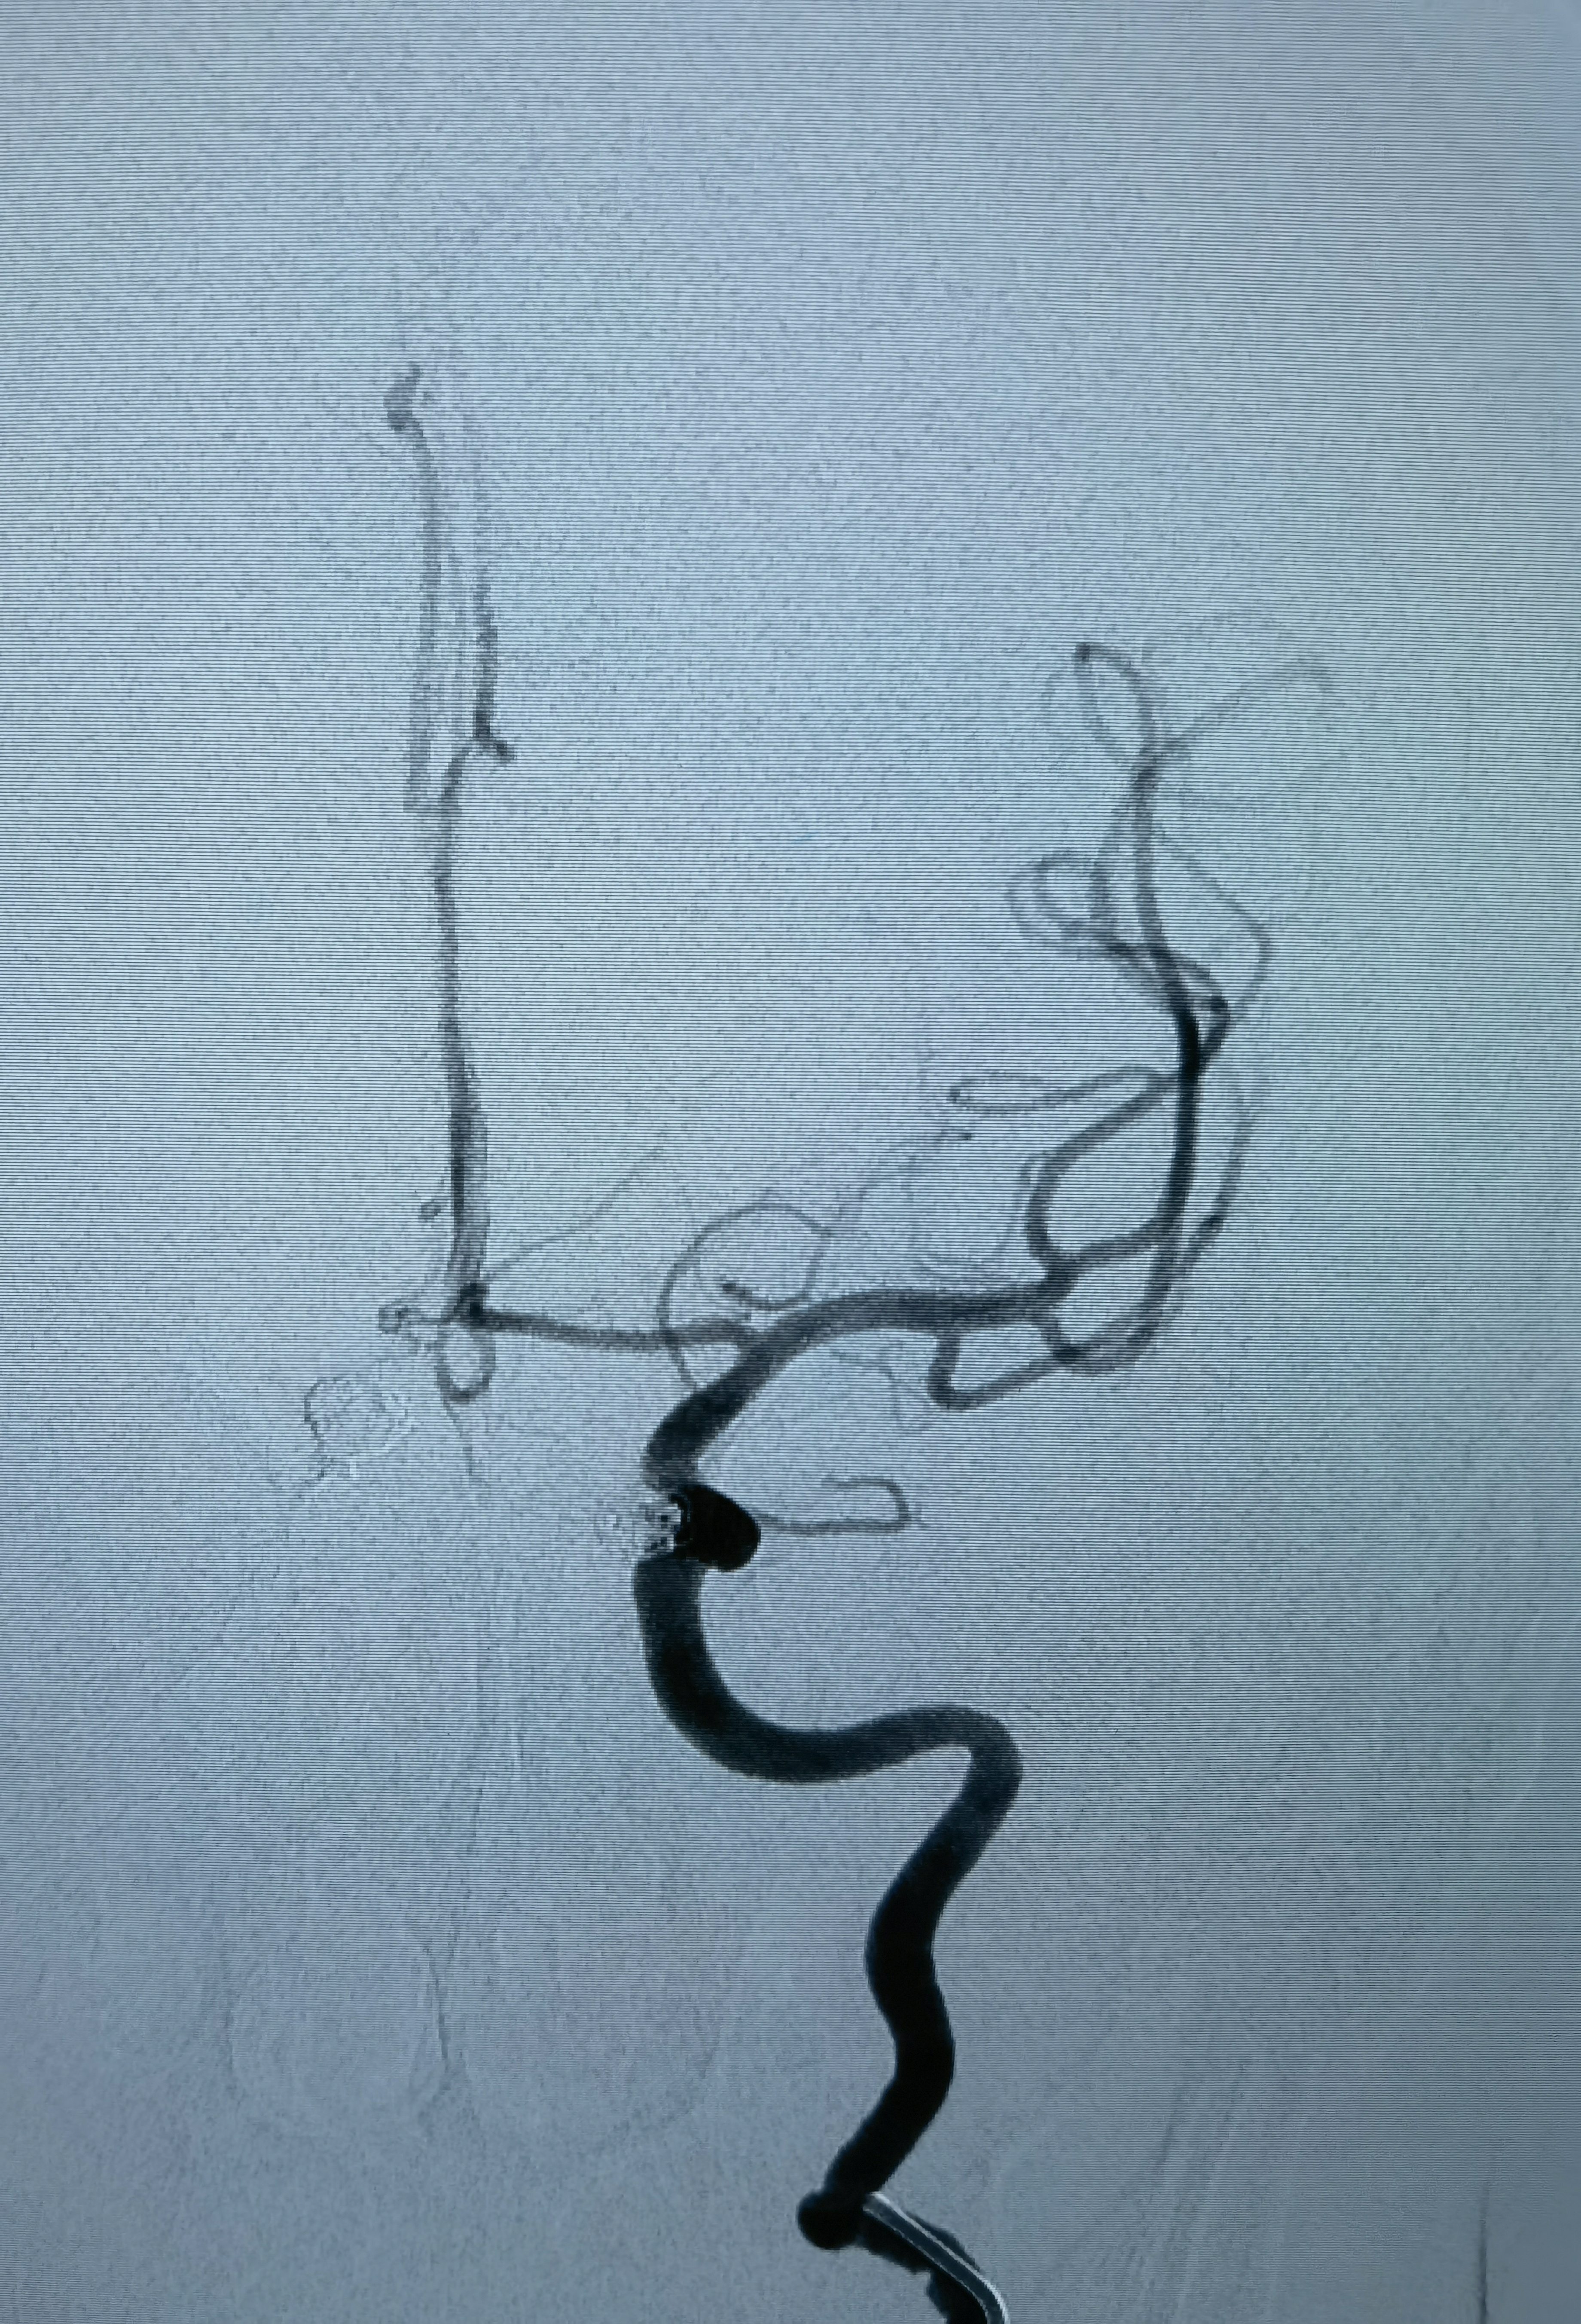

当地医院手术时造影,左侧颈内动脉眼动脉段动脉瘤

栓塞后

当地医院造影右侧颈内动脉床突上段瘤样突起,约1mm,未处理!